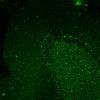

Neuronal Ceroid Lipofuscinosis (NCL) (5)